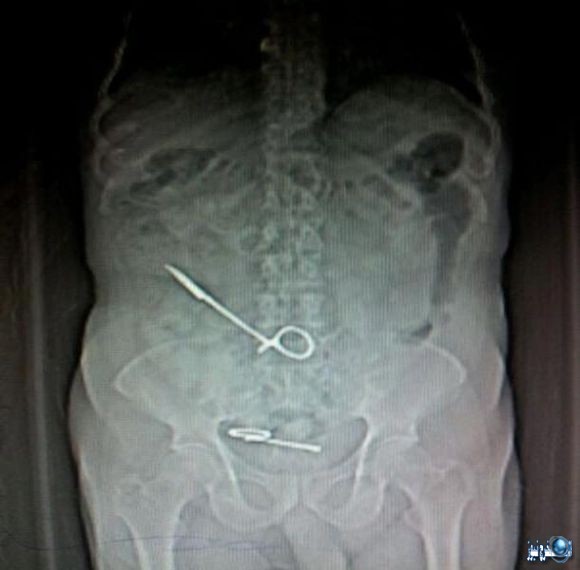

بتاريخ 18 يناير 2015، كشف المحضر رقم 336 إداري لسنة 2015 الذي حررته أسرة المريض وحيد كمال السيد “50 عاما”، في قسم شرطة العطارين بالإسكندرية، عن أن المريض دخل لإجراء عملية جراحية لاستئصال جزء من الأمعاء مطلع شهر ديسمبر الماضي، إلا أنه وعقب خروجه تعرض لمضاعفات صحية خطيرة.

وأضاف المحضر أن المريض المذكور عقب خروجه من المستشفى شعر بتحسن كبير في حالته الصحية حتى عاودته الآلام الشديدة، وقام بتوقيع الكشف الطبي وإجراء الأشعة إلا أن طبيب الأشعة المعالج اكتشف وجود مقص داخل بطن المريض بطول 40 سم، فتوجهت أسرته لإجراء أشعة بأحد المراكز الخاصة، وثبت صحة الأمر بعد أن أنكر الأطباء صحة الواقعة، مشيرين إلى أن ما حدث هو التهابات بالقولون.

واتهم المحضر 3 من الأطباء بالتسبب في هذا الإهمال، بعد أن حاولوا نفي الواقعة، وأكدوا ضرورة دخول المريض العناية المركزة مرة أخرى، وكتبوا له تصريح دخول مرة أخرى لإجراء جراحة جديدة لاستخراج المقص، بعدما أشاروا لأسرة المريض أن ما حدث أمر طبيعي ولا مخاوف على حالة المريض، فدخل المستشفى الثلاثاء الماضي وأجريت له الجراحة إلا أنه ومنذ هذا التاريخ وهو يعاني بسبب سوء المعاملة والإهمال.